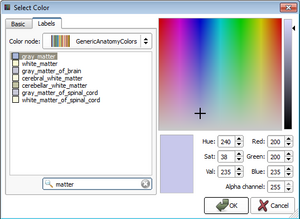

| qMRMLColorTableView |

|

A table view to display a color table model |